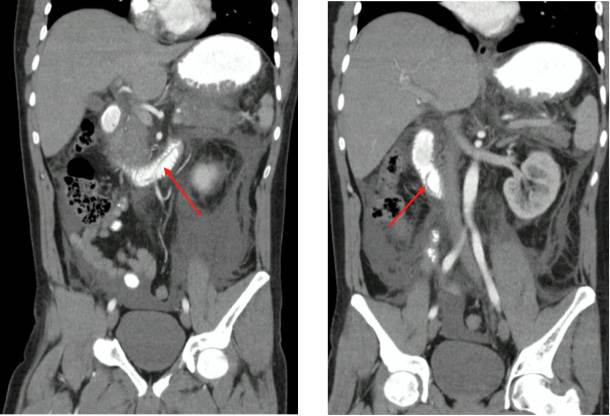

Figura 2 Tomografía de abdomen con doble contraste corte coronal que evidencia áscaris en la papila duodenal, segunda y tercera porción del duodeno (indicador rojo).

Masculino de 35 años de bajo estrato socioeconómico sin otros antecedentes. Ingresó a urgencias por dolor epigástrico súbito de intensidad severa. A la valoración sin alteración de signos vitales, sin signos de irritación peritoneal. Se descartó síndrome coronario agu do y perforación de víscera hueca. Estudios evidenciaron elevación de bilirrubinas, transaminasas, fosfatasa alcalina y en especial de amilasa. Se realizó diagnósti co de pancreatitis aguda (PA) sin evidencia de disfunción multior-gánica. Se completó estudio con ecografía de abdomen superior sin litiasis biliar, con colecciones en ambas goteras parietocólicas. Se indicó realizar una tomografía de abdomen computarizada con do ble contraste (TAC de abdomen) la cual identificó pancreatitis aguda (Figura 1) y defecto de llenado de morfología tubular localizado ha cia la papila duodenal (Figura 2). La endoscopia de vías digestivas altas (EVDA) reveló un único parásito de 25 cm ubicado en la papila duodenal. Tras cubrimiento antibiótico y desparasitación el paciente cursó a la quinta semana de seguimiento con pancreatitis necrotizante amura llada, requirió manejo con necrosectomía y drenaje de colecciones.